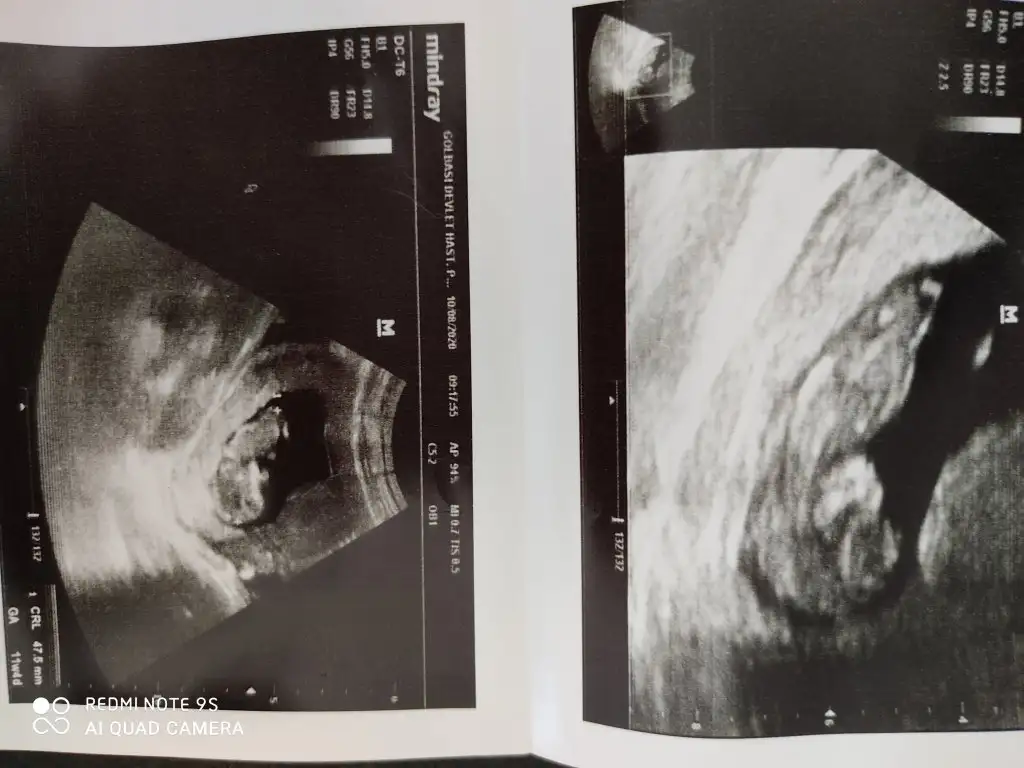

Yani çok da fazla ilgilenmedi doktor.Tayin sebebiyle şehir değiştirdik .Elimde bir de şu şekilde var rica etsem buna bakar mısınız?

IMG_20200810_113812.webp